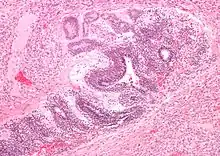

| Micrograph of the primitive neuroepithelium of an immature teratoma of the mediastinum. H&E stain. | |

The mediastinum has three main parts: the anterior mediastinum (front), the middle mediastinum, and the posterior mediastinum (back). Masses in the anterior portion of the mediastinum can include thymoma, lymphoma, pheochromocytoma, germ cell tumors including teratoma, thyroid tissue, and parathyroid lesions. Masses in this area are more likely to be malignant than those in other compartments.[2][3]